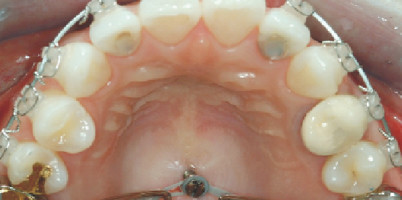

Hier wird ein neues Positionierungsverfahren für Lingualbrackets im Rahmen der indirekten Klebetechnik vorgestellt, für das kein Set-up benötigt...

Hier wird ein neues Positionierungsverfahren für Lingualbrackets im Rahmen der indirekten...